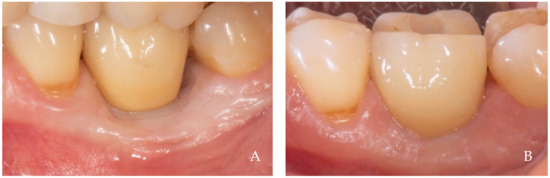

2. Clinical Examples of Oral Soft Tissue Growth